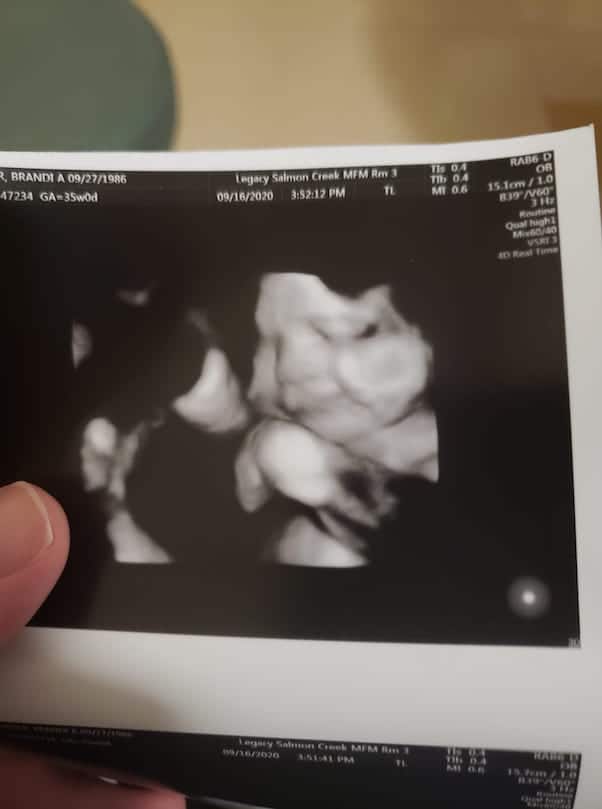

For starters, here’s the latest ultrasound that Brandi has shared. She posted it in late September, just under a month before her due date:

And here’s the complete caption Brandi wrote for the latest pic of her unborn second daughter:

This little lady wanted to share a big smile with everyone 😊 🥰. She will be here in just a few short weeks and we are so excited. I can’t believe I have been blessed beyond words and I’m so thankful for my babies each and everyday. Due to obvious reasons I won’t be having a baby shower. I want everyone to stay safe and healthy and happy. I have a Amazon baby registry though if anyone wants to spoil this little lady ❤. Please stay safe everyone.